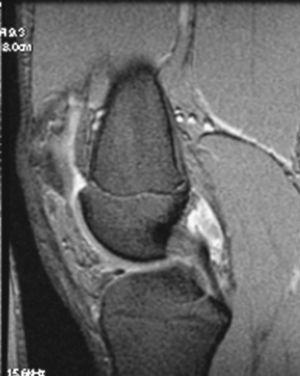

La RM muestra (figs. 1, 3 y 5):

Figura 1 RM. Imagen potenciada en T2 con supresión de grasa. Cuerpos libres en receso articular interno.

Figura 5 RM. Imagen potenciada en T1. Cuerpos libres alrededor de los ligamentos cruzados y en otras localizaciones intraarticulares.